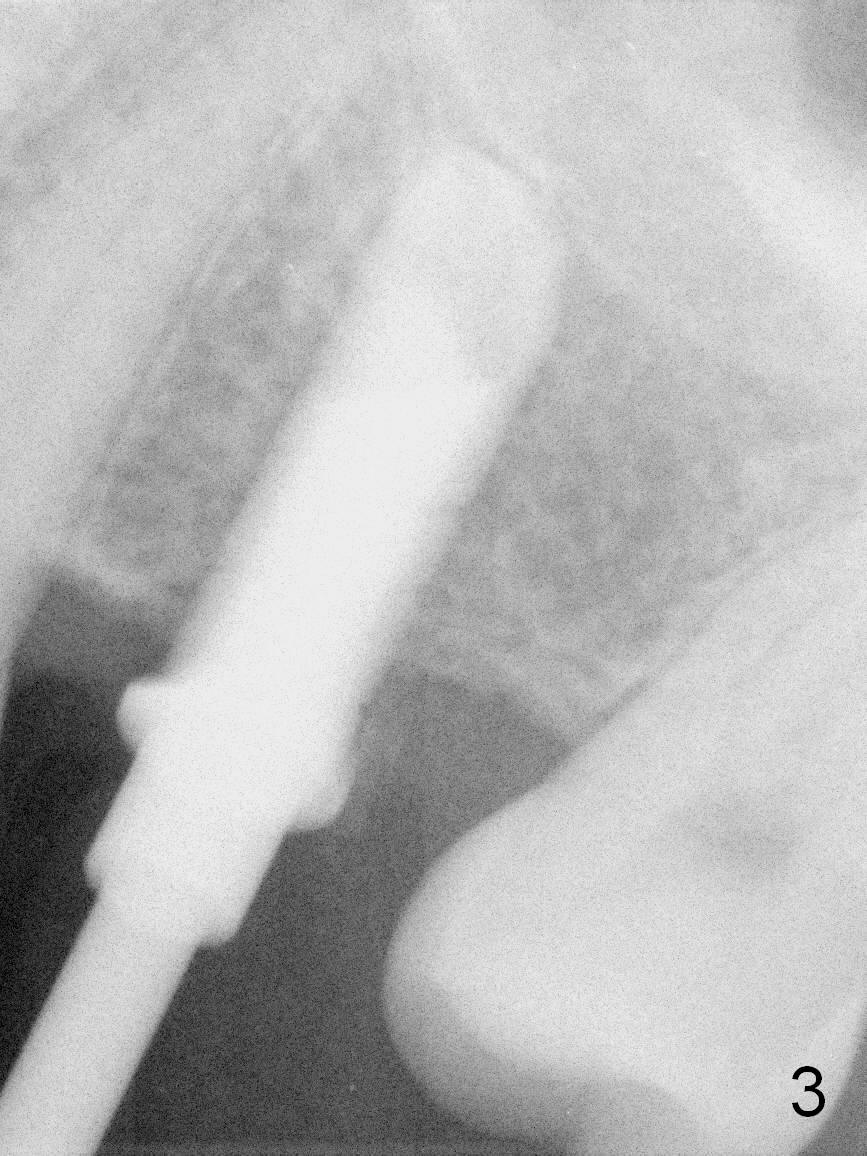

A 49-year-old man is an engineer. The tooth #14 is missing (Fig.1,2). He wonders how a one-rooted implant can replace a three-rooted tooth. Anyway, osteotomy is initiated at the site with 2.5 mm reamer in place (Fig.3). A 5x8 mm Bicon implant is placed (Fig.4). Seven and a half months later, the bone density next to the implant plateau appears to increase (Fig.5 arrowheads, as compared to Fig.4). The beauty of Bicon implant is that the crown (Fig.6 C) can be extraorally cemented to the abutment (A) prior to re-seating. Two years and 3 months post cementation, while no residual cement is visible, the bone density at the crest has increased (Fig.7 arrowheads). The crown is de-cemented 4 years 4 months post cementation; it appears that the abutment is small and short (5x2 mm 10 degree stealth). The bone density of the cortex around the implant (Fig.9 ^) is higher than that at #15 and #3.